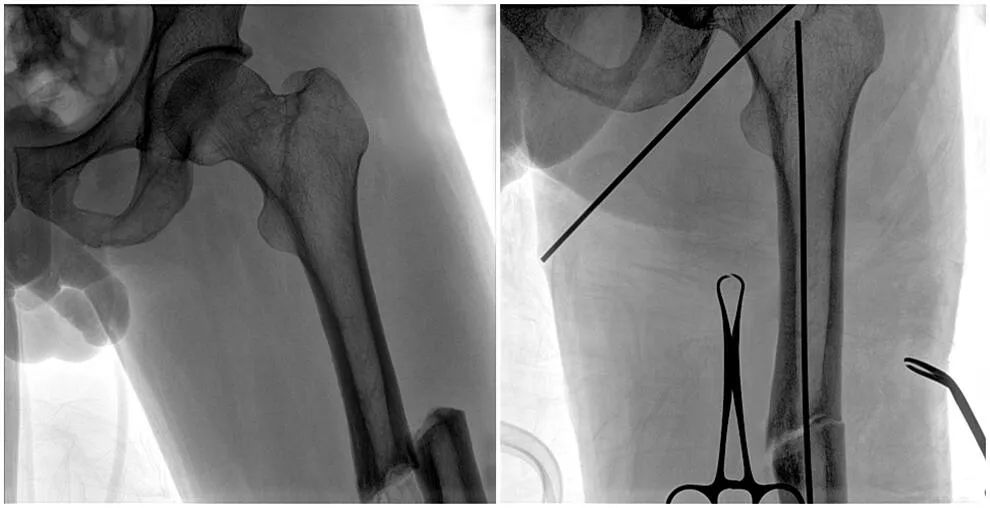

C形臂輔助手術(shù)過程

術(shù)中使用普愛醫(yī)療大平板一體式C形臂進(jìn)行透視,判斷骨折情況及克氏針、髓內(nèi)釘?shù)冉饘僦踩胛锏奈恢?,進(jìn)行調(diào)整。C形臂準(zhǔn)確的術(shù)中定位,大大縮短了手術(shù)的時(shí)間,減輕了患者的痛苦,輔助手術(shù)順利完成。

大平板一體式C形臂輔助手術(shù)過程